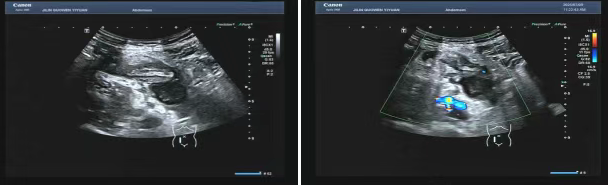

80 歲的張爺爺(化名)因前列腺增生前往國文醫(yī)院就診,泌尿外科為其開具了泌尿系超聲檢查。超聲科醫(yī)生在檢查過程中,憑借敏銳的觀察力,發(fā)現(xiàn)患者右下腹有異常混合回聲包塊。醫(yī)生沒有放過這一異常,立即展開進(jìn)一步探查,結(jié)果顯示包塊內(nèi)疑似有闌尾結(jié)構(gòu),且周圍組織存在粘連,還伴有液性暗區(qū)。考慮到老年患者病情往往較為隱匿,癥狀也不典型,醫(yī)生第一時間與臨床醫(yī)生溝通,建議進(jìn)行緊急處理。隨后,經(jīng)過臨床醫(yī)生詳細(xì)檢查,患者迅速辦理住院并接受手術(shù),術(shù)后病理檢查結(jié)果確診為 “闌尾壞疽伴穿孔合并膿腫形成”。

主治醫(yī)生介紹,老年人患闌尾炎時,癥狀常常不典型,很容易被誤診為腸胃炎或其他疾病。張爺爺僅表現(xiàn)出輕微腹脹的癥狀。倘若不是超聲檢查時意外發(fā)現(xiàn),極有可能延誤治療,進(jìn)而引發(fā)感染性休克,甚至危及生命。超聲檢查在這類急腹癥的篩查中,發(fā)揮了至關(guān)重要的作用。